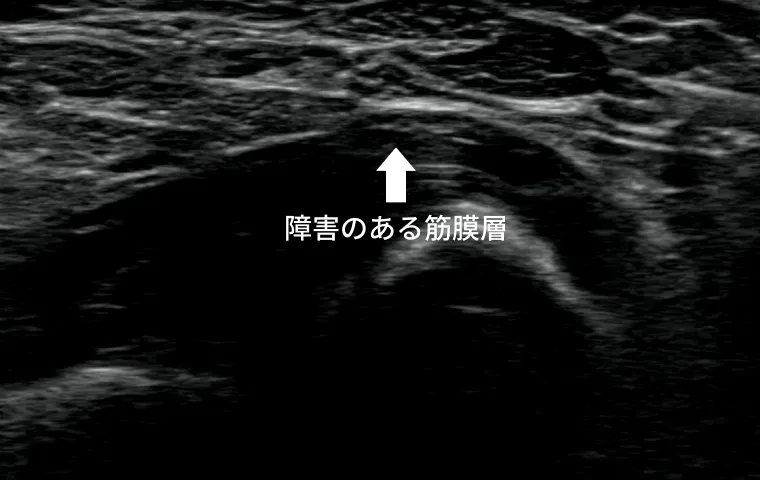

超音波(エコー)検査による観察技術の進歩により、筋膜や神経の滑走障害(こわばり・ひっかかり)をリアルタイムで可視化できるようになりました。

こうした滑走障害を起こしている部位に対して、生理食塩水などを注入しながら組織間の隙間を広げることで、痛みや可動域の制限を改善することが可能です。

「構造的な原因」にアプローチできる治療法として、再発予防にも効果が期待できます。

筋膜は本来、動作に合わせて伸び縮みし、筋肉や関節の動きをスムーズに保っています。

しかし、なんらかの要因によって、筋膜の滑走性(組織同士が滑るように動く性質)や柔軟性が低下し、隣接する組織との間に摩擦や引っかかりが生じることがあります。このような滑走障害が原因となり、筋肉の可動域が制限されたり、痛みや違和感が生じたりすることが知られています。